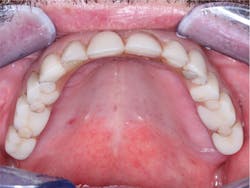

Figure 4: I placed this fixed prosthesis 20 years ago, and it had to have more facial fullness to reduce the typical sunken facial form. After 20 years of service, the irritation of soft tissue is still obvious.